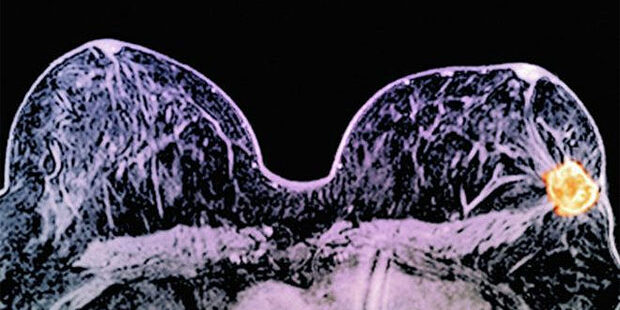

Elas foram questionadas se gostariam de fazer um teste genético para ver a presença de mutações nos genes BRCA 1 e BRCA 2 e, caso sim, se o fizeram.

Apenas 40% de todas as mulheres com alto risco relataram receber aconselhamento genético para ajudá-las a decidir ou entender os resultados. Das que foram testadas, 60% receberam aconselhamento. Reshma Jagsi, pesquisadora sênior no estudo, afirmou que os resultados são preocupantes porque os testes podem ser uma ferramenta poderosa para mulheres de grupos de risco.